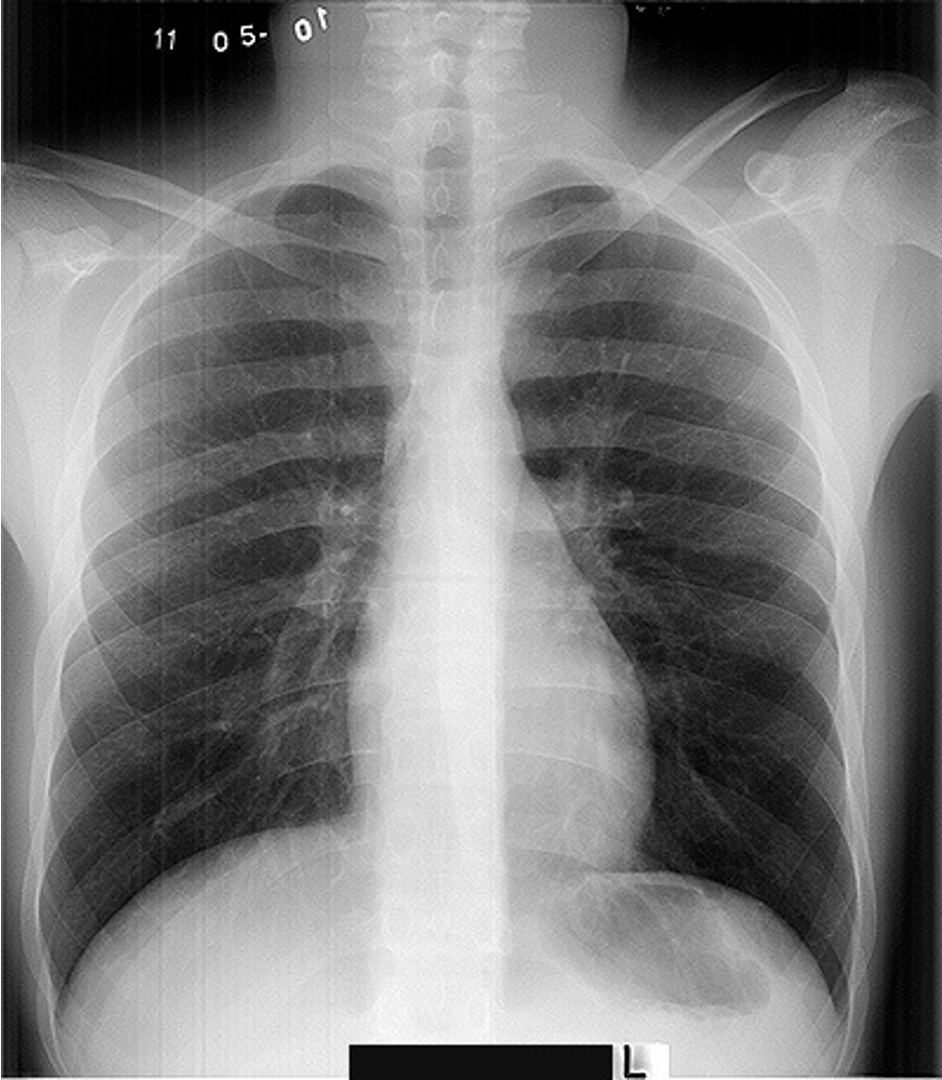

Normal CXR (PA & Lateral)